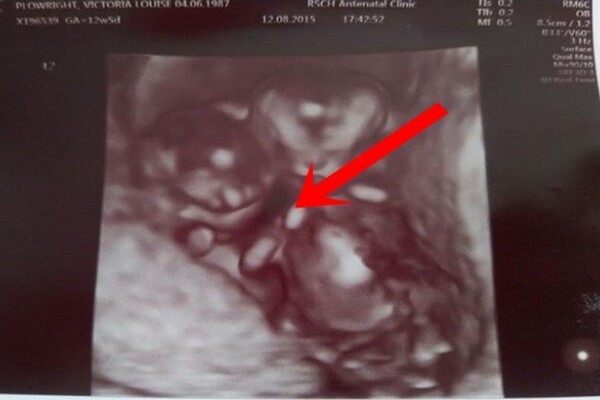

Khi trải qua các kỳ siêu âm, các bác sĩ đã phát hiện hai em bé nằm quá gần nhau, điều này không chỉ đáng lo ngại mà còn có thể dẫn đến rối dây rốn, một tình trạng nguy hiểm có thể gây thiếu oxy cho cả hai. Mặc dù có những cảnh báo nghiêm trọng, nhưng Vicky chưa bao giờ mất niềm tin vào khả năng sống sót của hai con.

Vượt qua mọi lo lắng, sự kiên trì và tình yêu thương từ gia đình đã góp phần làm nên điều kỳ diệu. Trong những tuần theo dõi thai kỳ, các chuyên gia phát hiện ra một điều vô cùng đặc biệt: hình ảnh của hai đứa trẻ ôm chặt lấy nhau trong túi ối, hai bàn tay nhỏ nhắn nắm chặt, tạo nên một cảnh tượng ấm lòng. Chúng tự tạo ra một vị trí ổn định để ngăn chặn dây rốn bị rối, thể hiện một liên kết vô hình nhưng vô cùng mạnh mẽ giữa hai anh em.